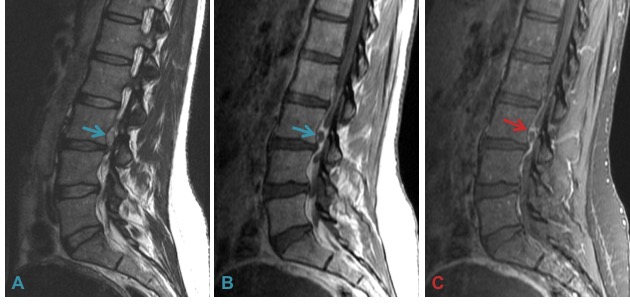

c) Cystic degeneration of herniated discs.

Rare cystic degeneration (A & B) is best identified on fluid-sensitive images (A). Fluid accumulation after disc surgery such as microdiscectomy results in a discal pseudocyst (C & D).